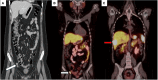

Episodic severe Cushing syndrome resulting from ectopic ACTH secretion (EAS) from appendiceal neuroendocrine tumor (NET) is extremely rare. Here, we describe a case of a 24-year-old woman with episodic severe EAS resulting from appendiceal NET with extensive metastatic disease. The patient presented with rapid weight gain, violaceous striae, fatigue, edema, and anxiety. Biochemical evaluation showed markedly elevated 24-hour urinary free cortisol greater than 10-fold above the upper limit of normal, and widely fluctuating peaks and troughs of serum cortisol and ACTH concentrations indicating episodic severe EAS. Surgery for primary malignancy was initially deferred because of the high risk of perioperative complications related to severe hypercortisolism. She underwent bilateral adrenalectomy as first-line definitive treatment for severe EAS. Four months after adrenalectomy, she underwent cytoreductive surgery for primary metastatic appendiceal NET. Subsequent peptide receptor radionuclide therapy and monthly lanreotide injections rendered her disease stable. Three years after the initial presentation, she continued to undergo active surveillance with maintenance lanreotide for residual but stable metastatic appendiceal neuroendocrine tumor. This case of a rare metastatic appendiceal NET with EAS demonstrates the importance of individualized management and highlights the need for consideration of prompt bilateral adrenalectomy for patients with severe Cushing syndrome.